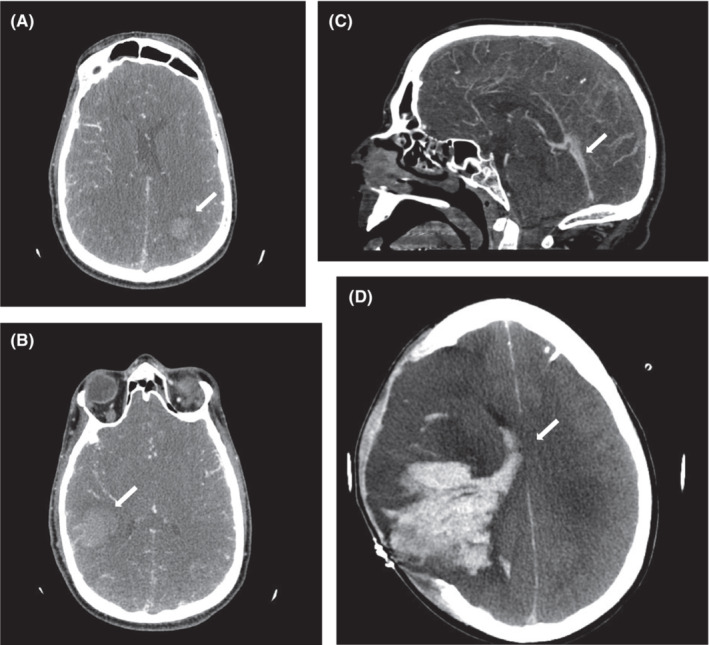

Platelet count was 108 × 109/L (norm: 150–400 × 109/L), slightly increased fibrinogen levels (441 mg/dl, norm: 180–350) and massively increased D‐dimers of 20.7 mg/L (norm: <0.55) were present. The platelet count nadir was 97 × 109/L. A computed tomography (CT) angiography revealed atypical intracranial bleeding in the presence of massive pansinus CVST and jugular venous thrombosis (Figures 1A–C). Initial treatment with heparin was changed to argatroban upon suspicion of VITT. 10 The patient received high‐dose intravenous immune globulin (IVIG; 1 g/kg body weight on two consecutive days) 11 which led to rapid normalization of platelet counts. The anti‐PF4/heparin IgG ELISA was highly positive (optical density [OD] > 3). The PF4‐dependent washed platelet activation assay, however, was negative. Together with the bleeding symptoms, especially the skin hematomas, this was considered evidence against the diagnosis of VITT.

FIGURE 1.

(A–C) Cranial CT on the day of admission to neurological ICU showing pansinus thrombosis with accompanying atypical intracranial bleeding (white arrows). (D) Cranial CT showing progression of intracranial bleeding and midline shift despite decompressive hemicraniectomy and external ventricular drainage 7 days after admission (white arrow).

Heparin was restarted and platelet counts remained stable. The patient's neurological status deteriorated due to intracranial hemorrhage (Figure 1D) with signs of elevated intracranial pressure (ICP). Despite all rescuing efforts, 31 days after vaccination, brain death was confirmed and organ donation followed. The autopsy revealed a widespread thrombosis of the superior sagittal sinus, transverse sinus, and confluence of sinuses with patchy hemorrhagic infarction and global cerebral edema, leading to tonsillar herniation. Additionally, disseminated thrombosis of small and medium‐sized vessels was identified at autopsy. Further genetic screening and coagulation diagnostics including vasculitis serology were all negative. The patient's original serum was retested using repository material and the washed platelet‐activation assay revealed platelet‐activating anti‐PF4 antibodies, confirming VITT. The assay at first time has been obviously false negative.